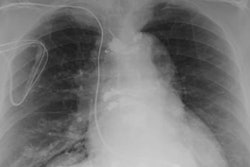

For this retrospective study, Tanaka and colleagues searched records at two Mayo Clinic facilities between January 2012 and June 2016 and found 25 patients who met the inclusion criteria. The team examined 28 prostate scans taken on 1.5-tesla MRI systems (Optima MR450w or Signa HDxt, GE Healthcare) with an endorectal coil and pelvic phased-array coil. All subjects had either an implanted pacemaker or ICD and were matched with patients with no CIEDs, who served as a control group (AJR, April 2019, Vol. 212:4, pp. 815-822).

The study also included two independent readers who rated image quality and artifacts on a five-point scale based on T2-weighted, diffusion-weighted, and dynamic contrast-enhanced images.

As for image quality, the team found no statistically significant difference between the two readers based on regional anatomy, artifacts, and overall imaging preferences in either the CIED group or control subjects. Their lack of differentiation also held true for the three MR imaging sequences individually and when combined.